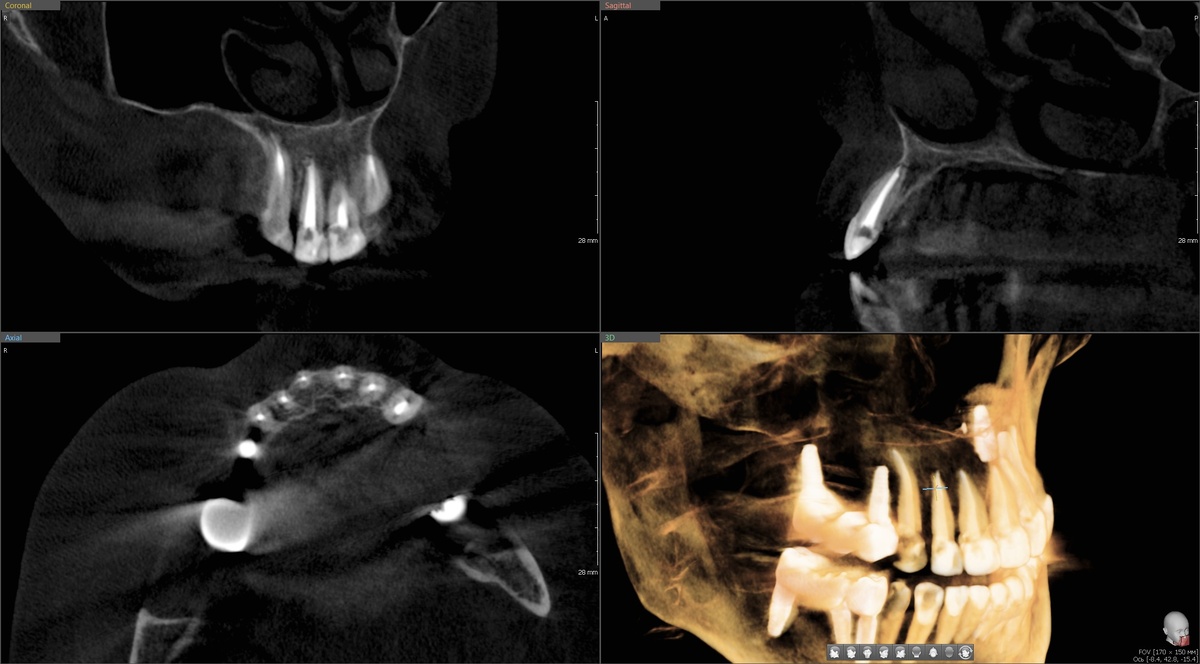

Удаление, одномоментная имплантация и костная пластика

Двойка на верхней челюсти - зуб непростой. Зачастую, анатомически, у многих людей в этой области альвеолярного отростка кости маловато, дефицит по ширине, корень почти прислоняется к наружной кортикальной пластинке.

Просто удалить и оставить заживать - значит, безвозвратно потерять ткани, которые потом не восстановить, получить провал в перспективе, оголение имплантата. Это плохая идея в любой ситуации, а здесь - так особенно.

Единственный разумный путь - одномоментная имплантация с костной пластикой, с подсадкой фрагментов бугра верхней челюсти.

Бугор - это костный выступ в области последних верхних моляров (8), один из немногих источников собственной костной ткани в полости рта. Ресурс ограниченный, конечный - у кого-то его больше, у кого-то меньше, у кого-то вообще его нет. Вот почему кость в обасти бугров нужно беречь - бывают ситуации, когда без него прогноз принципиально хуже.